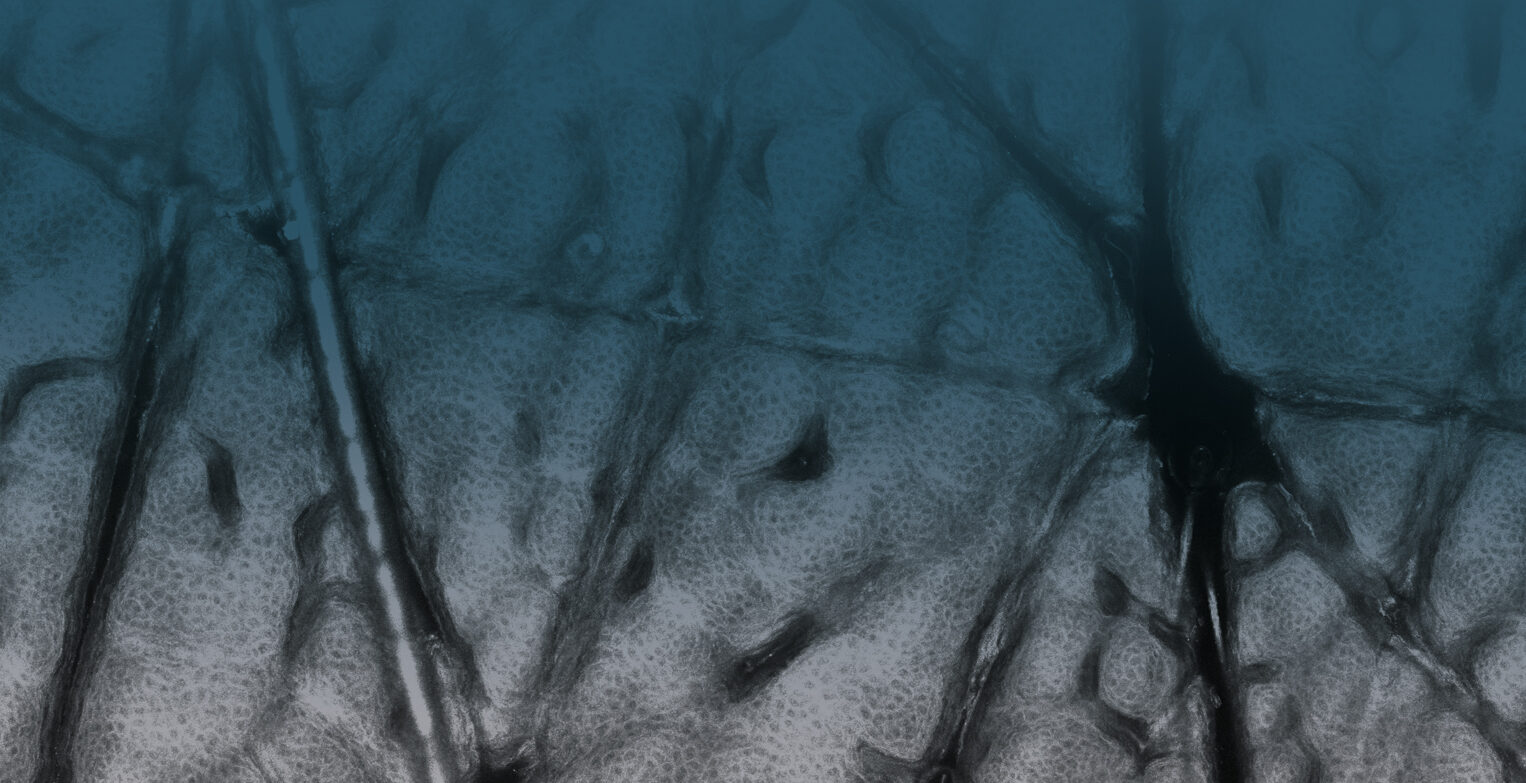

In Vivo examinations with the VivaScope technology using confocal laser scanning microscopy (CLSM) allow for an optical biopsy using a non-invasive procedure. See the different skin layers of your patients in real time.

All images courtesy of Prof. Dr Elke Sattler, Dr Martina Ulrich, Prof. Dr Julia Welzel